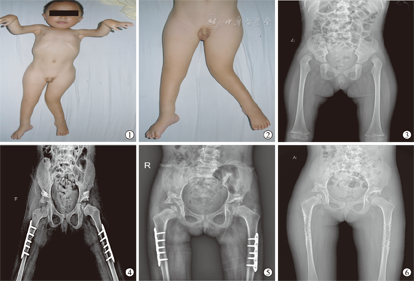

所有病例均获随访,随访时间2~5.2年,平均3.5年,其中2例步态基本正常,1例轻微跛行,2例步态不稳,1例需佩戴长腿支具行走,2例不能独立行走。4个髋关节活动基本正常,8个髋关节活动轻度受限,4个髋关节活动明显受限。根据Severin X线片评定标准和修改的McKay临床评定标准,优4髋,良8髋,中4髋,优良率为75%(图3,图4,图5,图6)。

本组髋关节屈伸活动范围左右两侧术后比术前提高约30°(表1)。其中,左髋关节术前活动度为70.4°±6.3°,术后活动度为104.1°±9.6°;右髋关节术前活动度为72.0°±10.2°,术后活动度为102.5°±8.9°,两者术前与术后比较,差异均有统计学意义(P<0.001)。本组有3髋出现股骨头坏死,Kalamchi and MacEwen分级Ⅰ、Ⅲ、Ⅵ型各1例(表2)。

AMC髋关节双侧脱位患儿应尽早进行手术治疗。Wada等[15]建议髋关节的切开复位时间应该等到10~18月龄,因为其治疗的大部分病例联合股骨和骨盆截骨术,而足、膝、髋畸形的矫正应在患儿3~10月龄同时进行,这样可以减少制动时间,降低关节僵硬的风险,使患儿更好适应社会。Stilli等[13]认为治疗的最佳年龄应在8~10月龄,足膝的畸形矫正时间分别为3~4月龄和6~7月龄,这样逐步矫正不会导致手术过程的复杂性。Szöke等[7]建议患儿在3~6月龄时行切开复位同时矫正足膝的关节挛缩,而年长患儿应行一期骨盆截骨及股骨短缩旋转截骨是更好的治疗选择。本组4例<12月龄患儿行了单纯前路切开复位手术,其中2例在5月龄行切开复位者,术后随访中4个髋关节活动基本正常(图7、图8),相比2例12月龄患儿,其髋关节活动范围显著增大、活动范围评分明显高,同时手术操作过程简单。因此,AMC髋关节双侧脱位患儿一经诊断,应早期选择手术切开复位,年龄越小手术过程也相对简单、术后髋关节临床效果越满意,此期间需同时进行其他部位畸形的矫正。

对于手术方式的选择,Szöke等[7]、Staheli等[16]和LeBel等[17]提出经内侧入路小切口切开复位可获得满意的疗效,其临床结果中显示该入路治疗的患儿比前外侧入路更能获得良好的髋关节功能和关节活动度。由于内侧入路已知伴有的股骨头坏死的高发生率[18,19],并且在治疗髋关节脱位中,最常用的是前路[3,17]和前外侧入路[5,8]。Wada等[15]认为,前侧入路能有效显露髋关节,去除阻挡头臼复位的因素(内翻的盂唇、肥厚的股骨头圆韧带、髋臼内增生的脂肪组织、髋臼横韧带,特别是挛缩增厚的关节囊),获得稳定的复位。本组病例均采用了S-P前侧入路联合内侧入路方式,该联合术式不仅可以良好显露髋关节彻底去除阻挡复位因素及松解挛缩紧张的内收肌,而且术中可行缝匠肌、股直肌、髂腰肌的松解,一定程度上纠正髋关节的屈曲挛缩畸形。Szöke等[7]认为,低龄患儿采取切开复位同时矫正足膝的关节挛缩,而年长患儿行一期骨盆截骨及股骨短缩旋转截骨。本组即采取这种治疗策略,6例患儿行单纯切开复位,2例行骨盆截骨及股骨短缩旋转截骨,结果显示优4髋,良8髋,中4髋,优良率为75%。